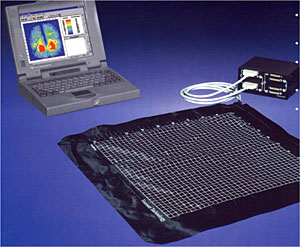

Technologia mająca na celu stworzenie Mapy Ucisku na skórę jest to narzędzie wykorzystujące komputer, niezbędne oprogramowanie, elastyczną podkładkę z czujnikami, jednostkę elektroniczną i źródło energii (Zdjęcie 1). Doktor Betz używa podkładkę z czujnikami wyprodukowaną przez Roho Group, Inc. Mierzy ona około 46 x 46 centymetrów i zawiera 1296 czujników, które odbierają impulsy kiedy wywierany jest na nie ucisk.

Zdjęcie 1: Oprzyrządowanie Mapy Ucisku: komputer z oprogramowaniem, podkładka z czujnikami oraz jednostka elektroniczna.